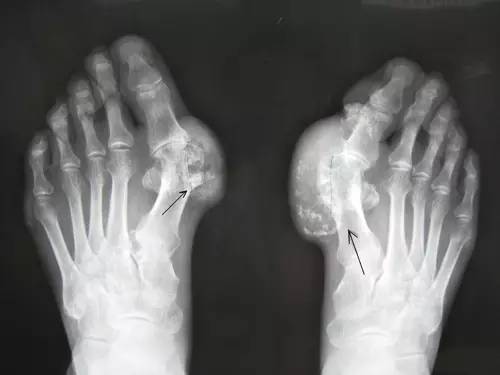

痛风第一危险物:高嘌呤

目前,痛风人群越来越年轻,20~40岁的中青年白领中有很多痛风患者。痛风其实就是我们常说的富贵病,年轻的时候如若吃得太好,缺乏运动,极易引发痛风。

痛风病人平时要少吃嘌呤高的食物,如海鲜、动物内脏、各种肉汤以及加工类食品如香肠、培根及各种饮料,可多吃新鲜蔬果。